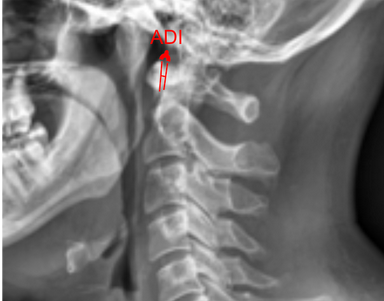

Image Type Cervical Spine X-Ray CT Scan MRI Scan Atlantodental Interval (ADI) Basion-Axial Interval Basion-Dens Interval (BDI) C2 Tilt C2–C7 Coronal Cobb Angle Cervical C2-7 lordosis C2-C7 Translation Chamberlain’s Line / McGregor’s Line Flexion-Extension George’s Line (Posterior Cervical Line) K-Line Interpedicular Distance (IPD) Occiput-C2 Angle Occipital Condyle–C1 Interval (CCI) Posterior Atlantodental Interval (PADI) Power’s ratio Sagittal Canal Diameter Sagittal Vertical Axis (SVA) Spinolaminar line Swischuk Line T1 Slope Torg/Pavlov Canal-to-Body Ratio